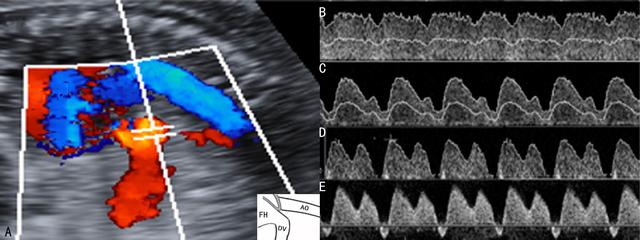

1.FFUA FFUA多普勒超声检查是最常用的FGR评估技术,通过该检查区别FGR的基本原因(图1)。在胎盘功能异常的早期,多普勒超声检查就可以发现FFUA血流阻力增加(图1C),同时,胎盘动脉的血流速度S/D以及PI也相应增加;胎盘功能严重受损时,可以出现舒张期血流消失(图1D),甚至反转(图1E),胎儿出生后围产期死亡率和发病率增加。有报道认为当胎盘三级绒毛血流闭塞超过70%时FFUA舒张期血流出现反向,并伴有严重的FGR(EFW小于3th百分位)和羊水过少。多普勒超声检查发现FUA血流的变化可以提醒临床医生进行早期干预,降低了不良妊娠结局的发生率。

图1 FGR时脐动脉血流速度曲线变化

A:脐动脉CDFI显示

B:正常脐动脉血流速度曲线

C:脐动脉血流速度曲线显示舒张期血流速度降低

D:脐动脉血流速度曲线显示舒张期血流消失

E:脐动脉血流速度曲线显示舒张期血流反向流动